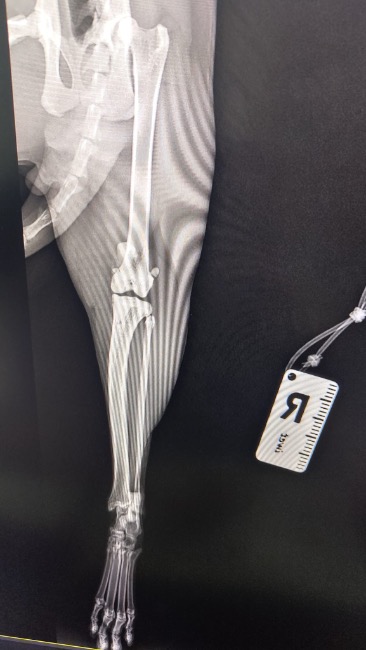

Zdiagnozowano u niego ciężką niestabilność obu rzepek, która sprawia, że każdy krok jest niepewny i bolesny. Dodatkowo lewa tylna kończyna wymaga specjalistycznego zabiegu TGR — wszczepienia protezy bloczka kości udowej.

To bardzo skomplikowana i kosztowna operacja, ale jedyna szansa, by Tymianek mógł normalnie chodzić i żyć bez cierpienia.

❗ Bez operacji jego stan będzie się tylko pogarszał!

Ból będzie narastał, pojawią się zwyrodnienia, a Tymianek — choć jeszcze taki młody — może zostać skazany na trwałe kalectwo. Już teraz widać, że ogranicza ruch, bo po prostu się boi.

🩺 Lekarze nie mają wątpliwości — czas ma tu ogromne znaczenie. Operacje stabilizacji obu rzepek oraz zabieg TGR muszą zostać wykonane możliwie szybko. Niestety ich koszt znacznie przekracza możliwości naszej fundacji. Dopóki nie zbierzemy chociaż części potrzebnej kwoty (która finalnie może okazać się wyższa), nie jesteśmy w stanie zapisać go na te zabiegi. 💔💔💔